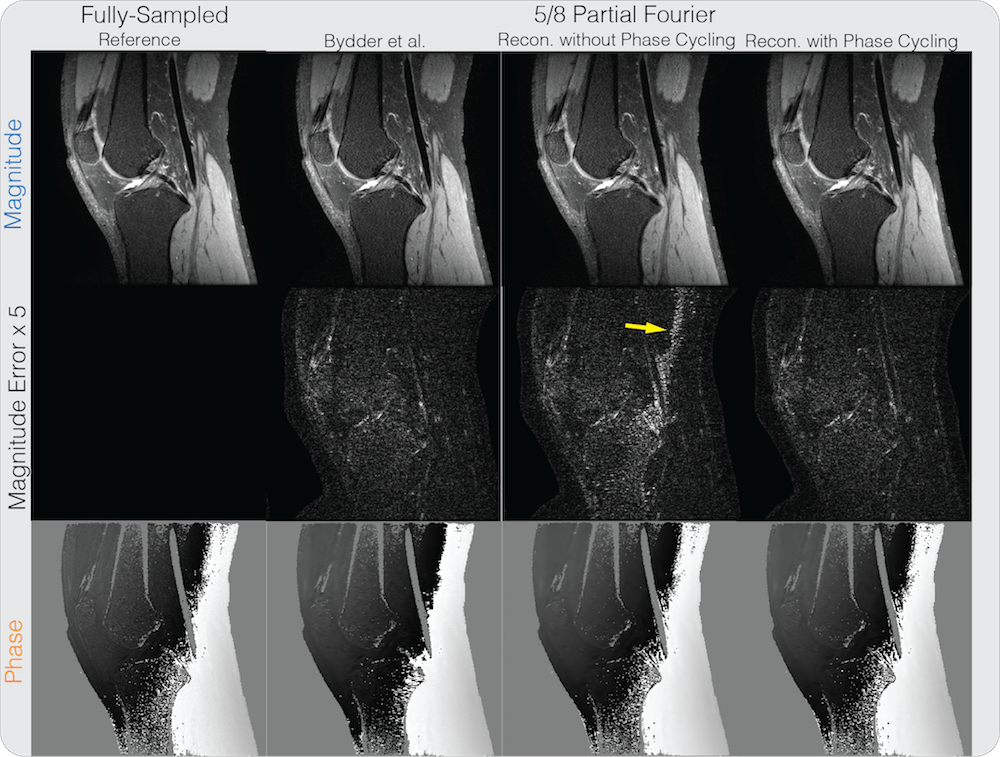

Supporting Figure S1 shows the partial Fourier reconstruction results combined with PI on the knee dataset. The figure compares the proposed reconstruction with and without phase cycling along with the homodyne reconstruction method described in Bydder et al. [17]. For the reconstruction without phase cycling, significant artifacts near the phase wraps can be seen in the magnitude image, as pointed by the yellow arrow. The proposed reconstruction with phase cycling also performs comparably with the state-of-the-art and did not display significant artifacts. In terms of PSNR, the method of Bydder et al. resulted in 34.55 dB, the proposed method without phase cycling resulted in 32.83 dB, and the proposed method with phase cycling resulted in 34.93 dB. One instance of our Matlab implementation of the proposed method took 4 minutes and 6 seconds.

S1

Partial Fourier + PI reconstruction results on a knee dataset. Without phase cycling, significant artifacts can be seen in the magnitude image near phase wraps in the initial solution, pointed by the yellow arrow. With phase cycling, these artifacts were reduced and the result is comparable to the robust iterative partial Fourier method with wavelet described in Bydder et al.